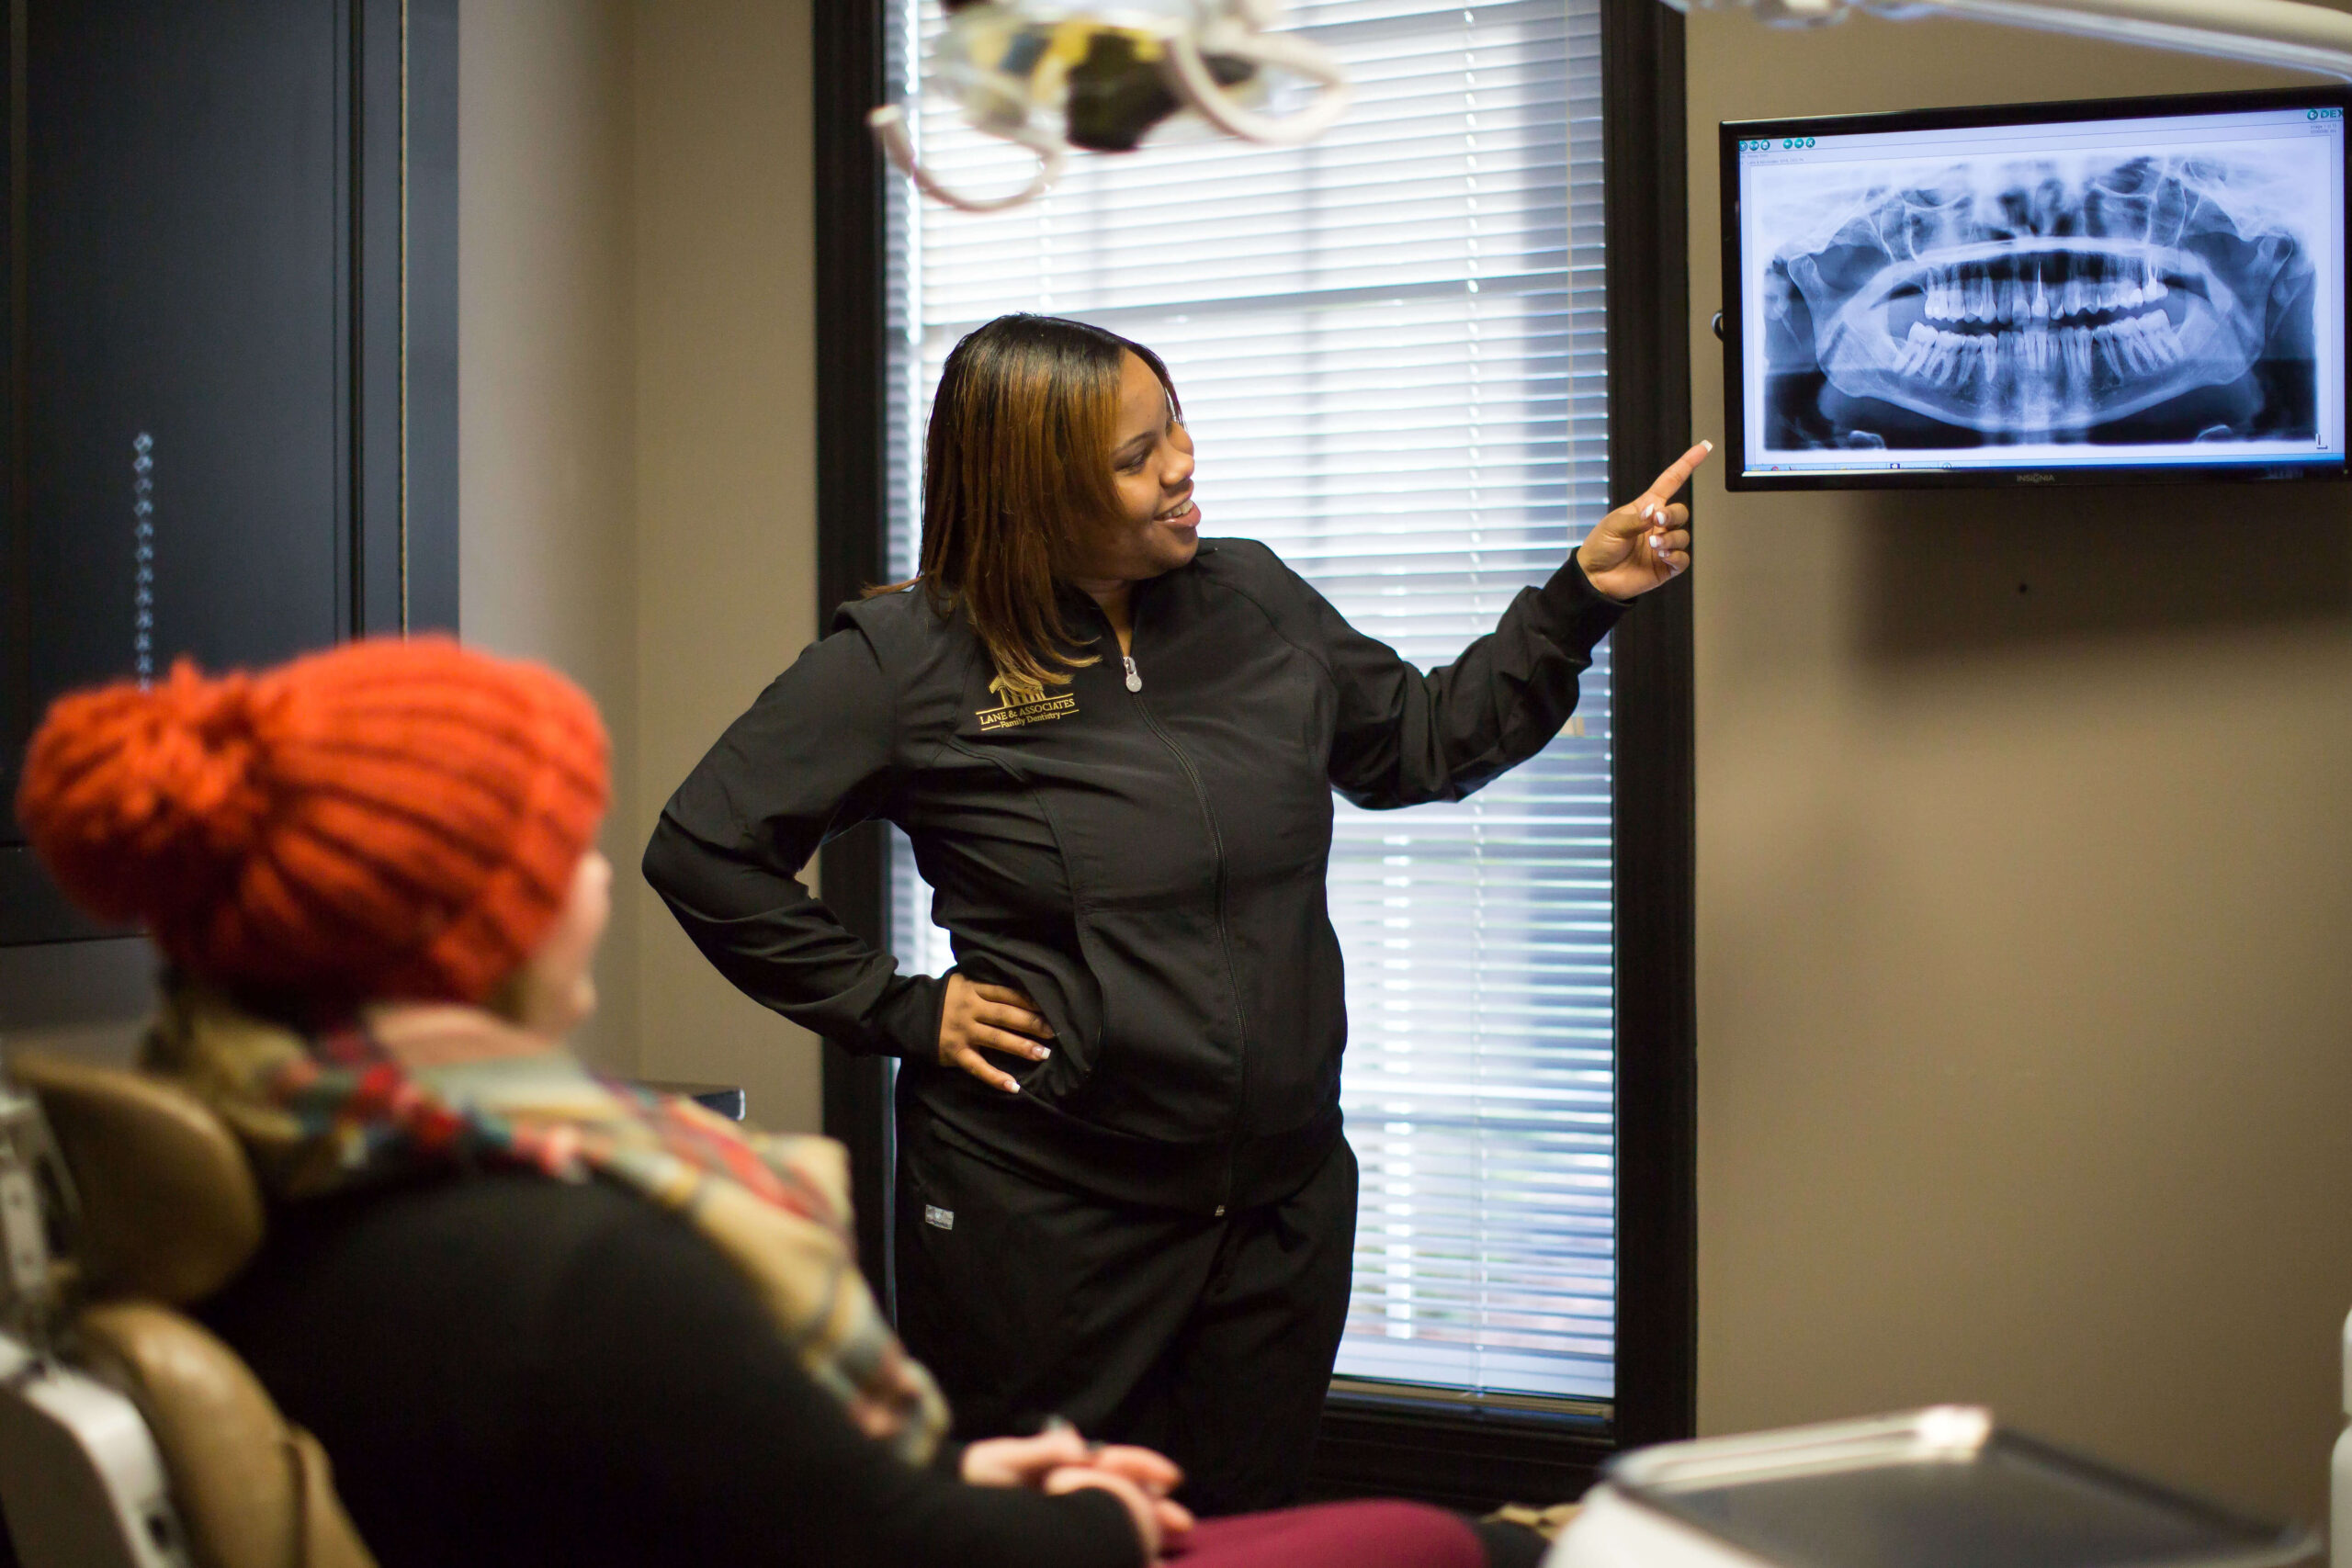

Our dental X-rays are designed to both minimize your exposure to radiation and provide your dentist with a clear image of your teeth’s internal structure to ensure the accurate and efficient diagnosis of current or potential dental issues, such as:

At Lane & Associates, dental X-rays are provided in tandem with our dental exams and teeth cleanings. However, not every appointment at our dental offices will require dental X-rays (we typically recommend a dental X-ray every few months to years, depending on your current age and dental health status). We do have pediatric bitewings available for the comfort of our younger patients, as well as patients with smaller mouths or strong gag reflexes.

We’ll begin with an initial examination of your teeth, gums, and mouth, as well as your head and neck pathology. A dental X-ray may be performed as well.